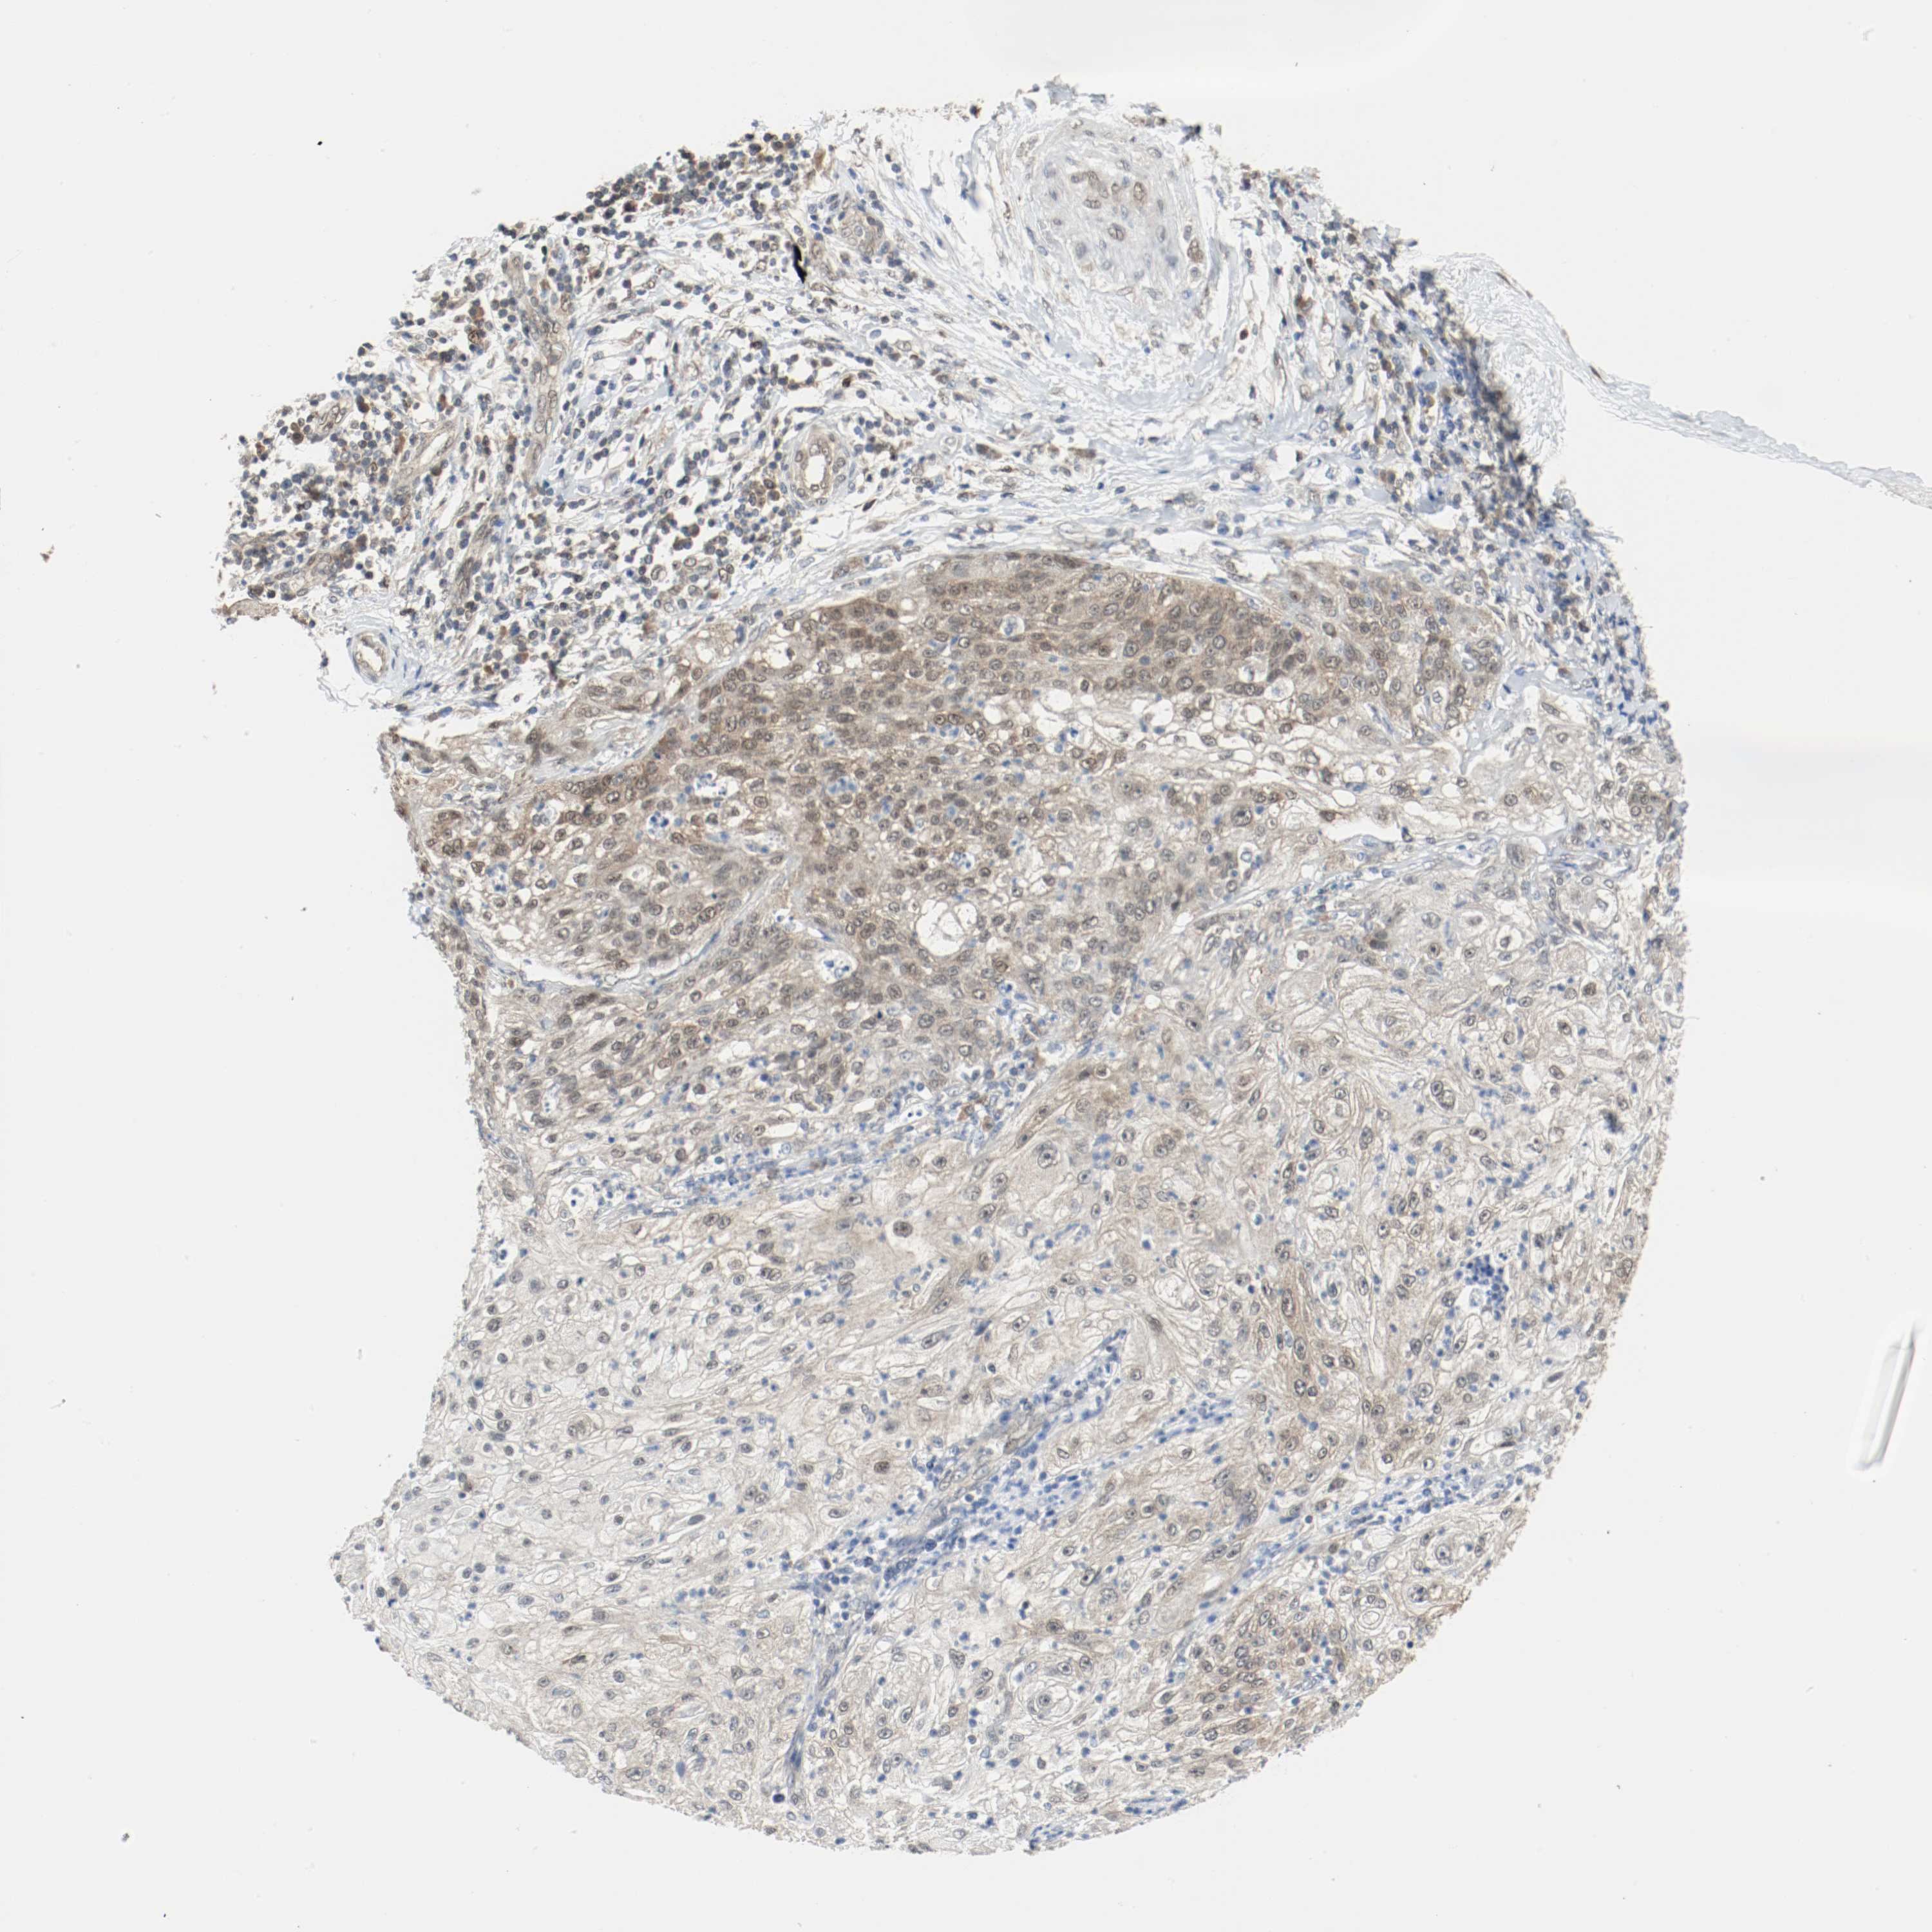

PPME1 is potential prognostic, high expression is unfavorable in Lung Adenocarcinoma (validation)

Best expression cut offi

When clicking on this number, the vertical dashed line indicating cut-off, the interactive survival plot, and the Kaplan-Meier curve will be adjusted to show results based on the best expression cut-off.

: 37.1

Average pTPM 37.1

Number of samples 105